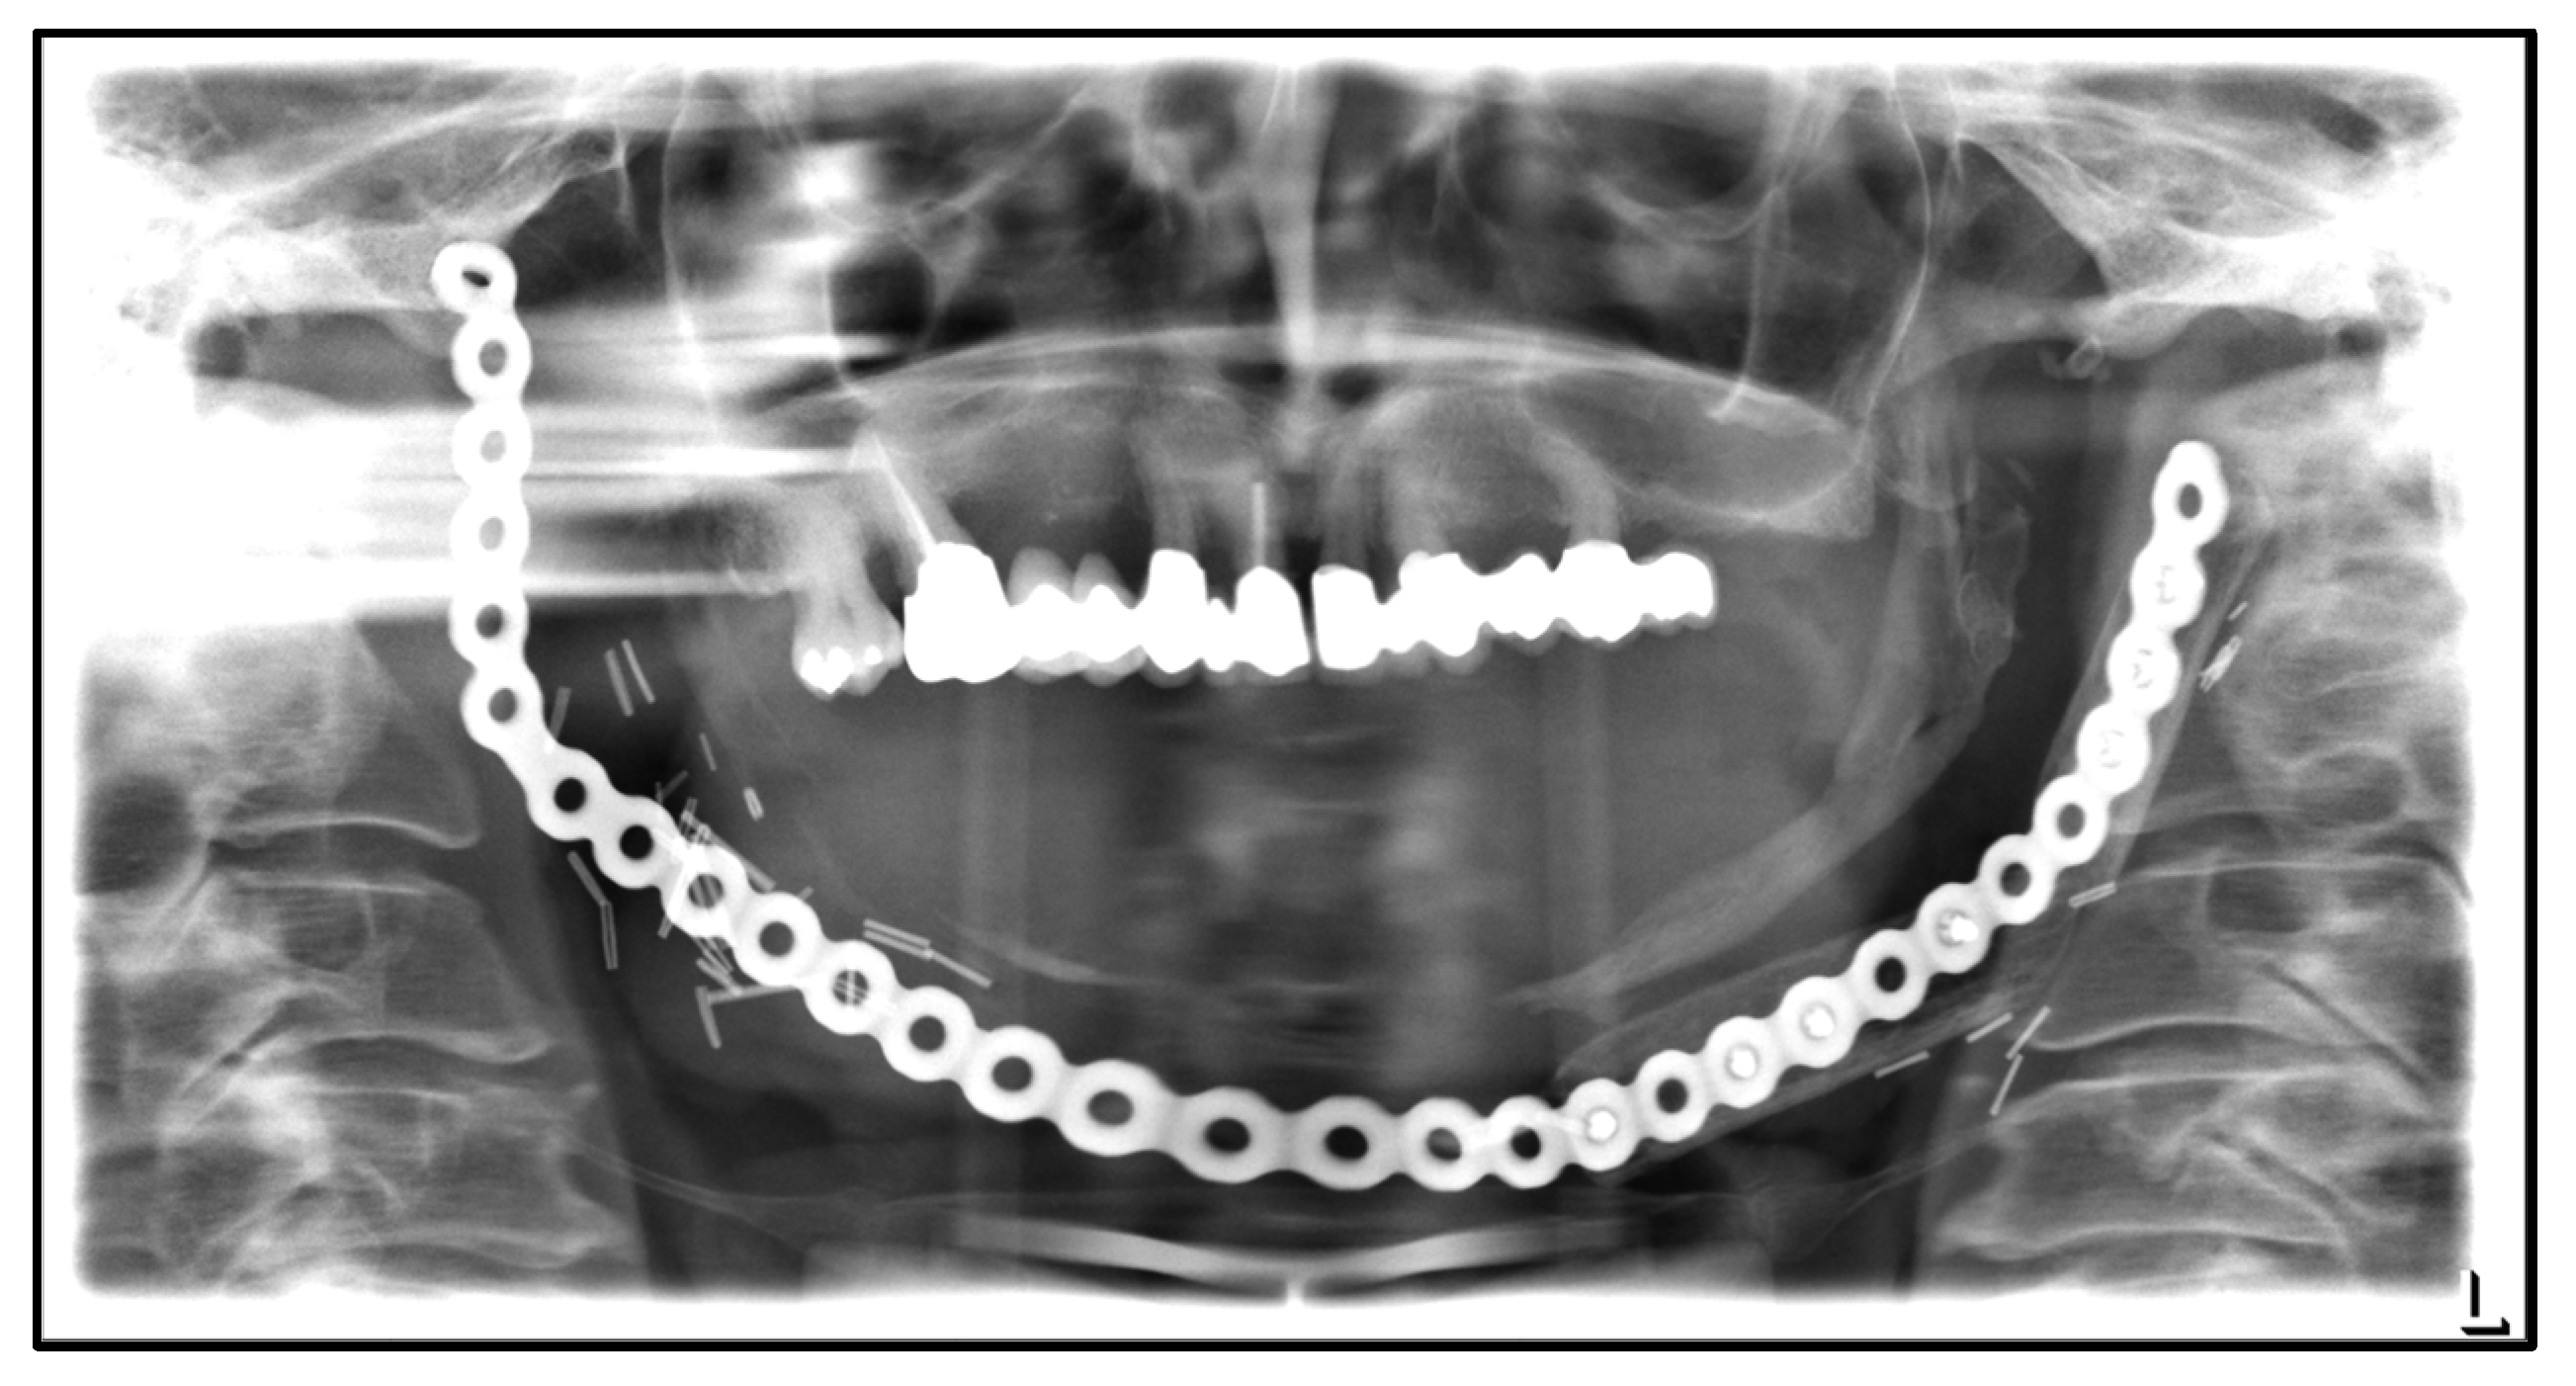

| September 2022: | Partial mandibular resection from the left mandibular angle to the right mandible, including the right temporomandibular joint, CAD/CAM-guided reconstruction with a bilateral free scapula flap with skin island, and patient-specific plate. In the course: